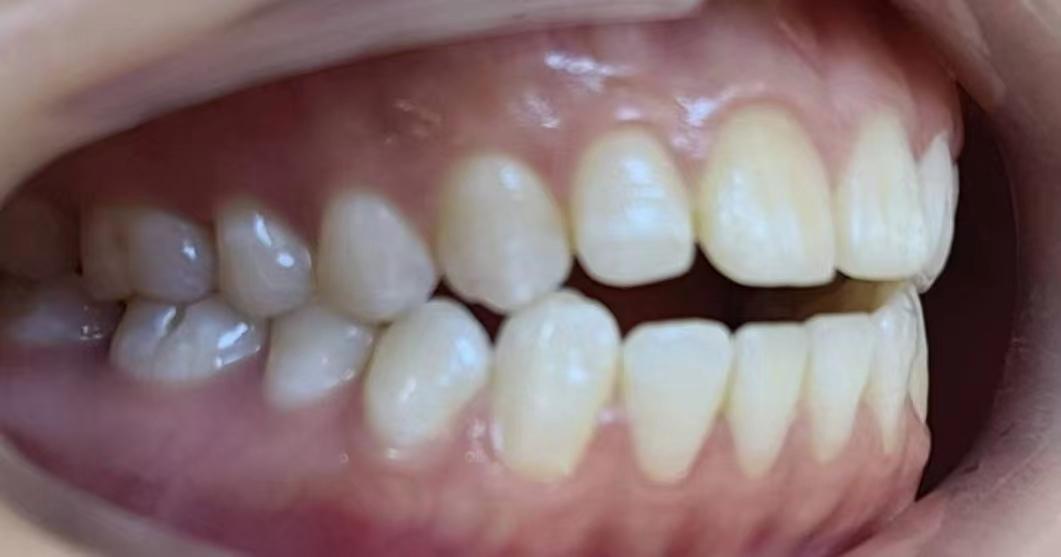

嘴凸不說(shuō)下巴還后縮

沒(méi)有美美的側(cè)顏殺怎么拿下心動(dòng)男孩呢?。?/span>

咱不提倡整容!但咱天生的下巴要給他使喚出來(lái)吧!所以很多妹紙沒(méi)有下巴有可能不是天生的呢!